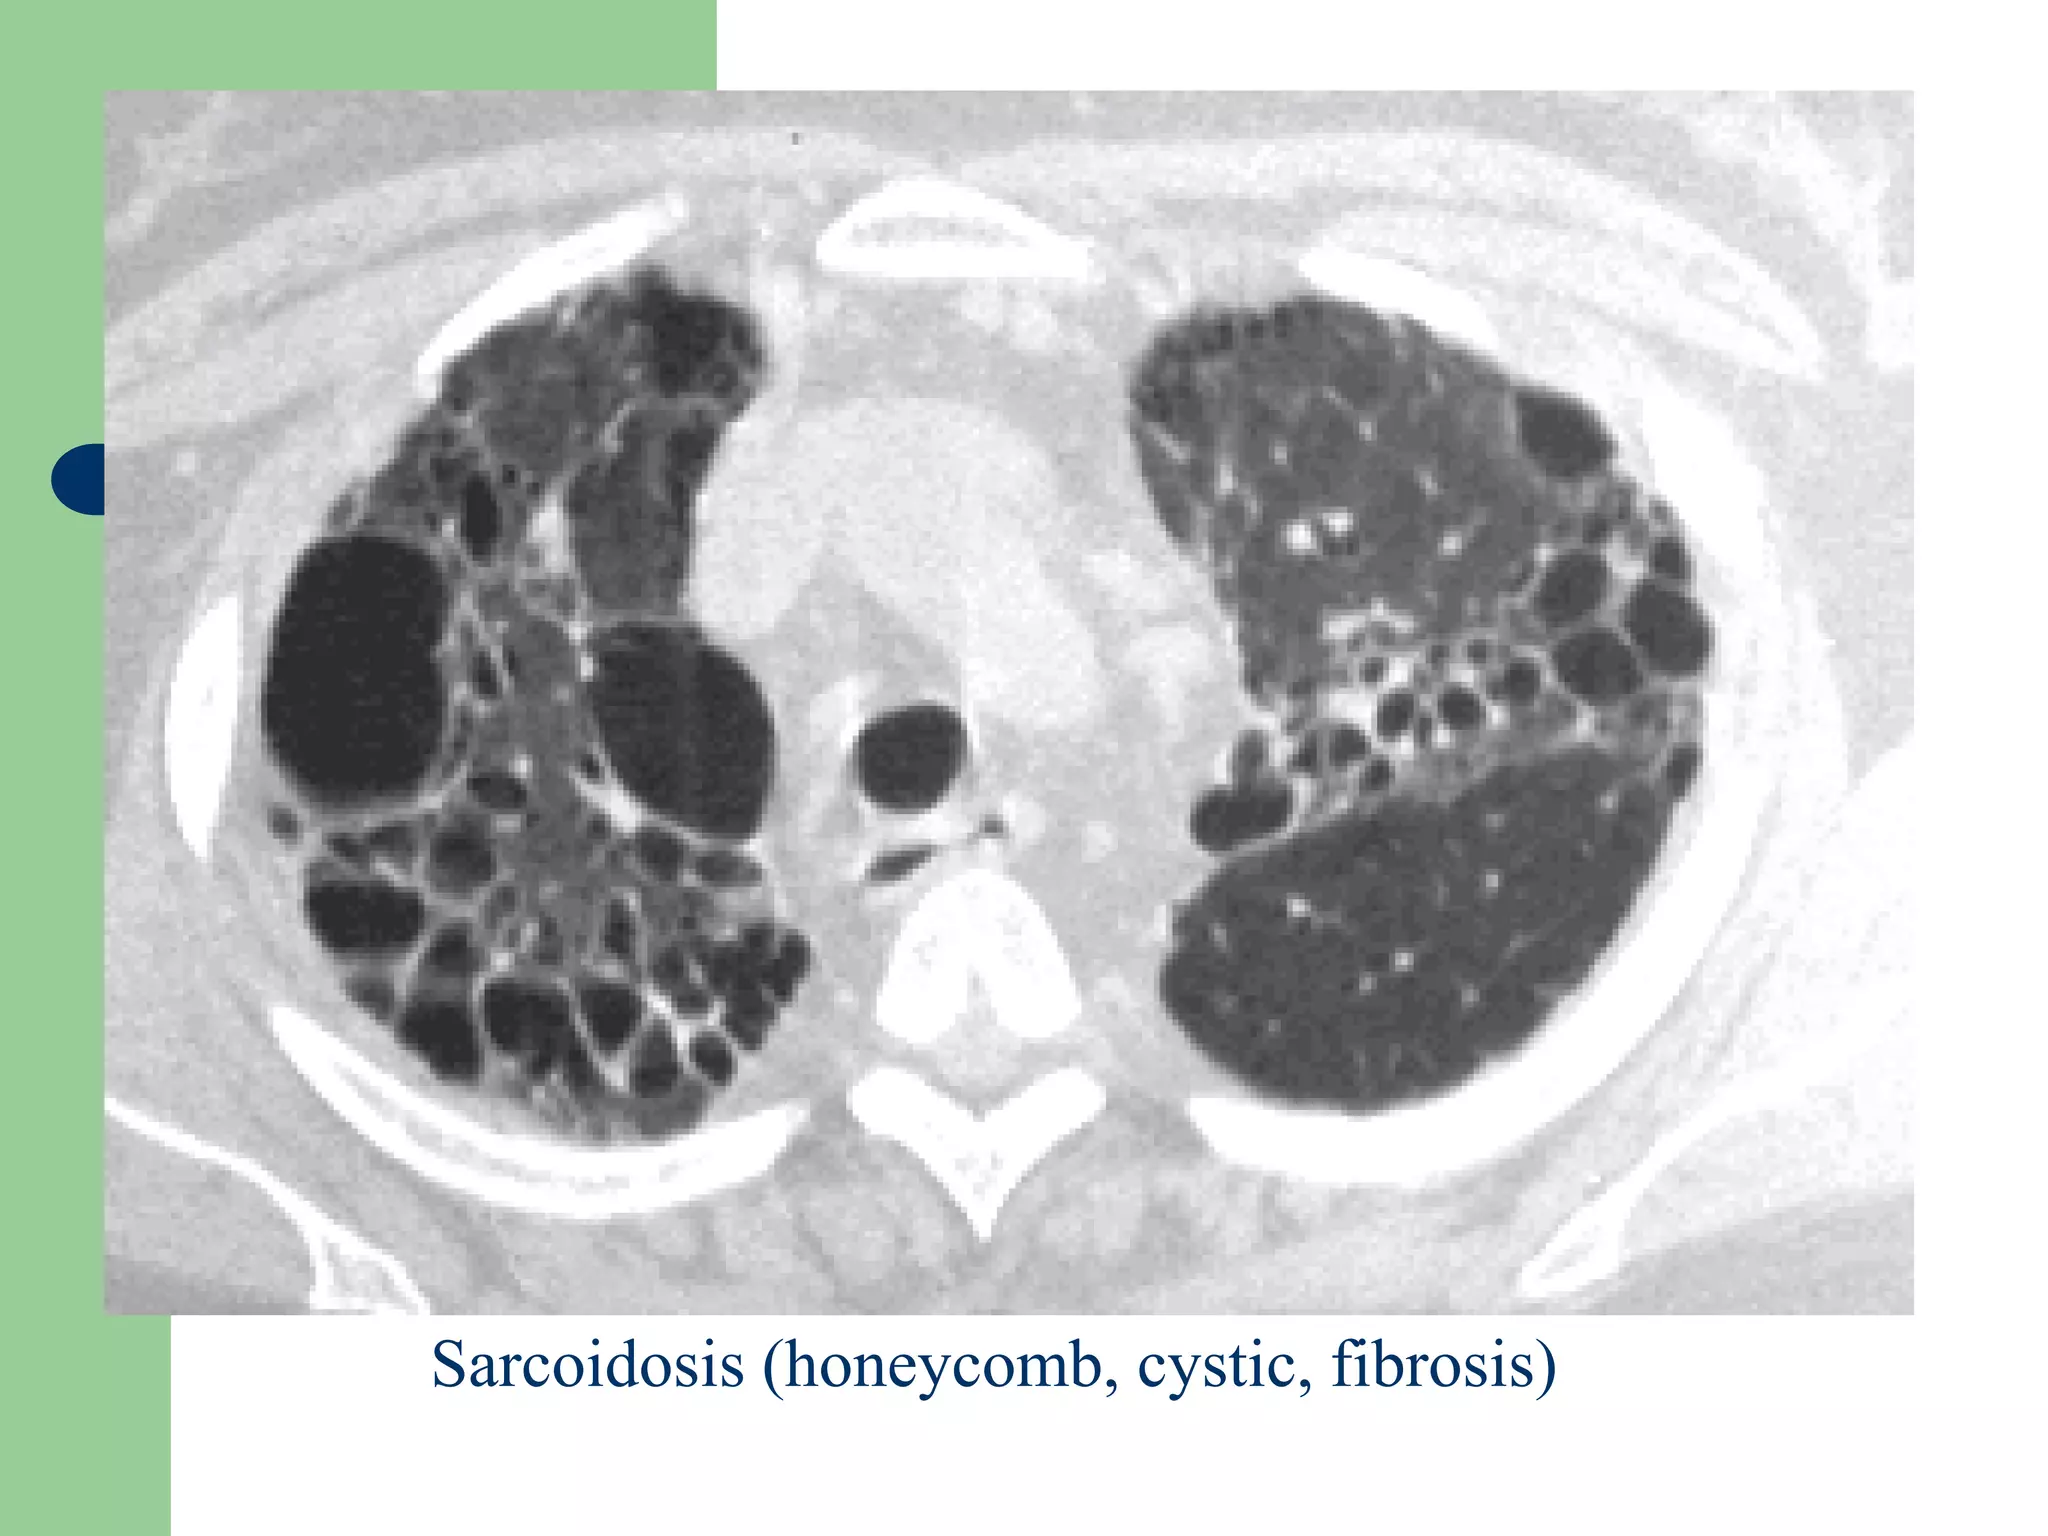

Dấu hiệu bệnh mô kẻ mãn

Maøng phoåi taïng khoâng ñeàu

-Daïng löôùi

-nhoû, neùt: sôùm, nheï

-thoâ: 75% buïi phoåi, sarcoidosis, vieâm phoåi keû maõn tính

-Noát: 90% nhieãm khuaån, beänh moâ haït, di caên, buïi phoåi,

-Ñöôøng: phuø moâ keû (tim), di caên baïch maïch..

-Toå ong:

Daøy vaùch lieân tieåu thuøy,

Sarcoidosis (honeycomb, cystic, fibrosis)